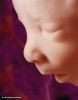

5 - 6 týdnů